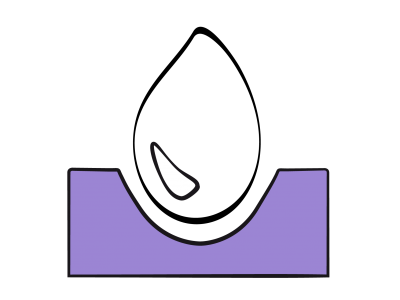

La fonction diastolique représente la capacité du ventricule à accommoder un remplissage adéquat sous un régime de pression basse et sur un vaste éventail de conditions de charge (voir Chapitre 5 La diastole). La dysfonction diastolique se réfère à une anomalie des indices échocardiographiques du remplissage ventriculaire qui reste cliniquement asymptomatique sauf à l'effort majeur, alors que l’insuffisance diastolique, responsable de près de 50% des insuffisances cardiaques congestives, est un syndrome clinique qui se caractérise par une dyspnée et une élévation chronique des pressions de remplissage (POG > 16 mmHg) en présence d’une fonction systolique préservée (FE > 0.5) [2,4]. Dans tous les cas, la pression télédiastolique ventriculaire est plus haute pour un même volume de précharge [2,7]. Une dysfonction diastolique est toujours présente en cas d’insuffisance ventriculaire systolique.

La fonction diastolique représente la capacité du ventricule à accommoder un remplissage adéquat sous un régime de pression basse et sur un vaste éventail de conditions de charge (voir Chapitre 5 La diastole). La dysfonction diastolique se réfère à une anomalie des indices échocardiographiques du remplissage ventriculaire qui reste cliniquement asymptomatique sauf à l'effort majeur, alors que l’insuffisance diastolique, responsable de près de 50% des insuffisances cardiaques congestives, est un syndrome clinique qui se caractérise par une dyspnée et une élévation chronique des pressions de remplissage (POG > 16 mmHg) en présence d’une fonction systolique préservée (FE > 0.5) [2,4]. Dans tous les cas, la pression télédiastolique ventriculaire est plus haute pour un même volume de précharge [2,7]. Une dysfonction diastolique est toujours présente en cas d’insuffisance ventriculaire systolique.